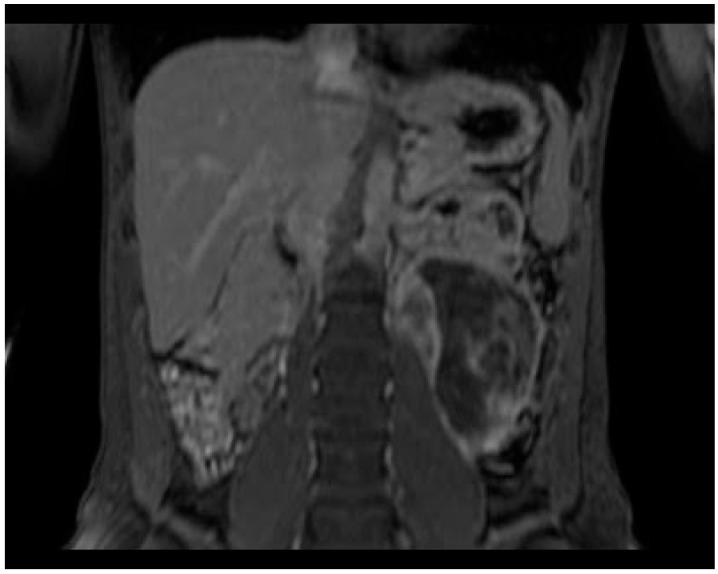

Retroperitoneal ganglioneuroma is a rare neuroectodermal tumor with a benign nature. We performed a literature review among 338 studies. We included 9 studies, whose patients underwent CT and/or MRI to characterize a retroperitoneal mass, which was confirmed to be a ganglioneuroma by histologic exam. The most common features of ganglioneuroma are considered to be a solid nature, oval/lobulated shape, and regular margins. The ganglioneuroma shows a progressive late enhancement on CT. On MRI it appears as a hypointense mass in T1W images and with a heterogeneous high-intensity in T2W. The MRI-"whorled sign" is described in the reviewed studies in about 80% of patients. The MRI characterization of a primitive retroperitoneal cystic mass should not exclude a cystic evolution from solid masses, and in the case of paravertebral location, the differential diagnosis algorithm should include the hypothesis of ganglioneuroma. In our case, the MRI features could have oriented towards a neurogenic nature, however, the predominantly cystic-fluid aspect and the considerable longitudinal non-invasive extension between retroperitoneal structures, misled us to a lymphatic malformation. In the literature, it is reported that the cystic presentation can be due to a degeneration of a well-known solid form while maintaining a benign character: the distinguishing malignity character is the revelation of immature cells on histological examination.

腹膜后神经节细胞瘤是一种罕见的良性神经外胚层肿瘤。我们对338项研究进行了文献综述。我们纳入了9项研究,这些研究中的患者接受了CT和/或MRI检查以对腹膜后肿块进行特征性描述,该肿块经组织学检查证实为神经节细胞瘤。神经节细胞瘤最常见的特征被认为是实性、椭圆形/分叶状以及边界规则。神经节细胞瘤在CT上表现为渐进性延迟强化。在MRI上,它在T1加权图像上表现为低信号肿块,在T2加权图像上表现为不均匀高信号。在综述的研究中,约80%的患者描述有MRI“漩涡征”。原始腹膜后囊性肿块的MRI特征不应排除实性肿块的囊性演变,并且在椎旁位置的情况下,鉴别诊断算法应包括神经节细胞瘤的可能性。在我们的病例中,MRI特征可能提示为神经源性性质,然而,主要为囊液成分以及腹膜后结构之间相当大的纵向无侵袭性延伸,使我们误诊为淋巴管畸形。在文献中,据报道囊性表现可能是由于已知实性形式的退变同时保持良性特征:区分恶性特征是组织学检查中出现未成熟细胞。